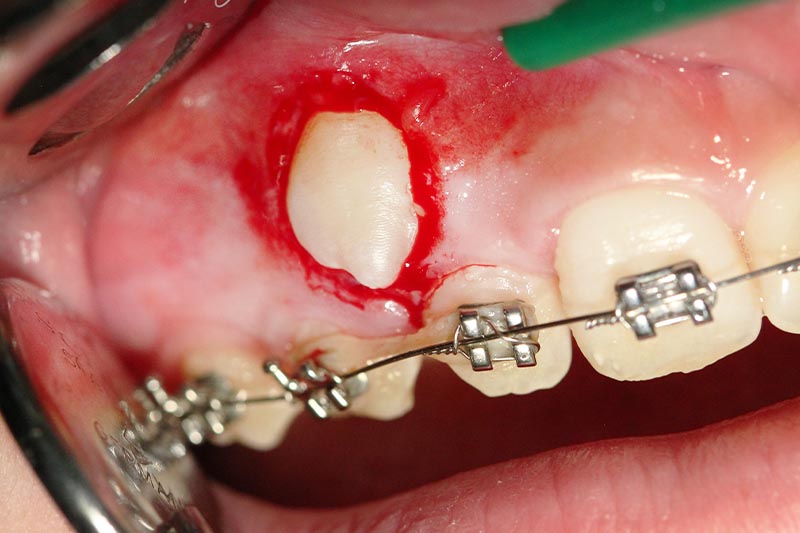

Diese retinierten Zähne, oft Eckzähne oder Prämolaren, können operativ entfernt werden. In günstigen Fällen können diese Zähne jedoch chirurgisch freigelegt werden und durch kieferorthopädische Maßnahmen in den Zahnbogen eingereiht werden.